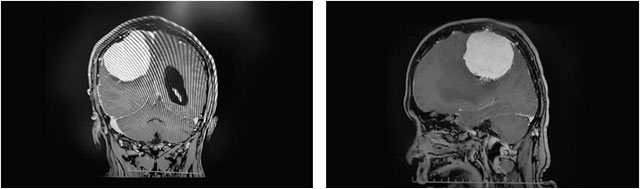

患者头颅MRI提示,右侧顶部大脑凸面可见一团块状异常信号影,边缘清晰,轮廓光整,大小约为6.1×5.7×5.1cm,体积巨大,形同鹅蛋状;毗邻额顶叶、基底节区见片状长T1、长T2水肿信号影,邻近脑组织受压移位变形,右侧侧脑室受庄变窄,中线结构向左侧偏移。

▲ 肿瘤位于右侧顶叶部

李士其教授介绍,杜先生脑中的这颗脑膜瘤位于右侧顶叶部,大脑的运动功能区内,对肢体神经造成了压迫,这也是导致杜先生左手手指麻木、无力,左侧大腿麻木的主要原因。而且由于拖延一年没有尽早手术治疗,肿瘤已经长到鹅蛋般大小,直径约达6公分。“患者的这颗肿瘤体积很大,对周边的运动功能区神经造成严重压迫,随时都有让患者瘫痪的可能,也为手术操作带来巨大挑战。而且肿瘤与大血管粘连,血供极其丰富,手术中一旦有丝毫差错,都有可能造成术中大量出血,直接威胁到患者的生命安全。”